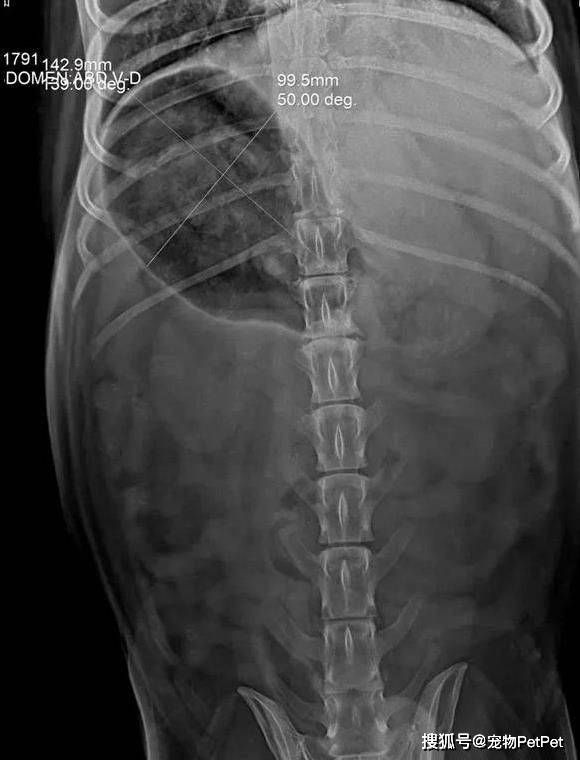

深夜的宠物急诊室里,一只名叫Mo的哈士奇瘫在诊疗台上,铲屎官用颤抖的手点开手机里的X光片——清晰的影像中,两个完整的龟壳轮廓赫然嵌在狗的胃袋里,如同两枚随时引爆的定时炸弹。

“它连佛牌都吞过,这次竟活吞乌龟!”主人声音发紧;兽医的眉头拧成了结:X光显示龟壳边缘锐利,Mo的肠道已有感染迹象,更棘手的是它年岁偏大。